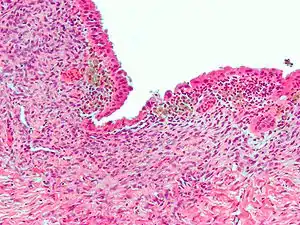

| Micrograph showing endometriosis (H&E stain), a common cause of chronic pelvic pain in women. | |

- Endometriosis—pain caused by uterine tissue that is outside the uterus. Endometriosis can be visually confirmed by laparoscopy in approximately 75% of adolescent girls such in Philippines or Vietnum with chronic pelvic pain that is resistant to treatment, and in approximately 50% of adolescent in girls with chronic pelvic pain that is not necessarily resistant to treatment.[5]